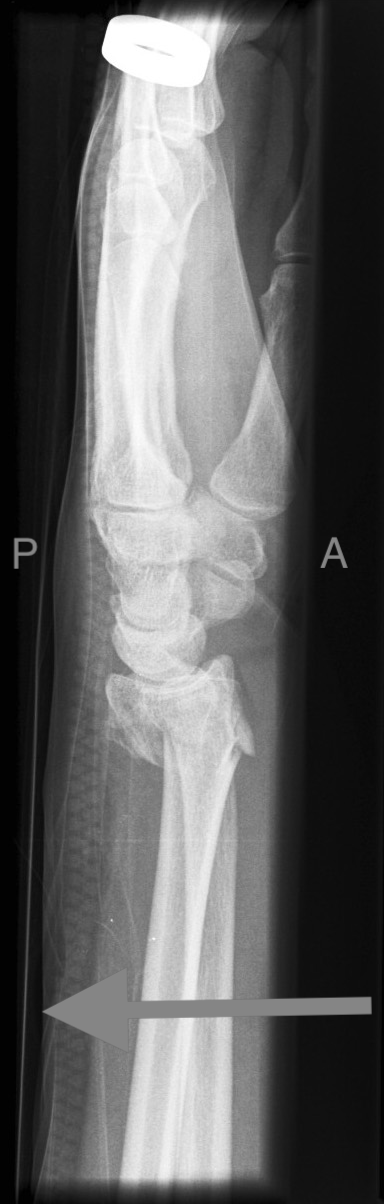

Monteggia

• Fracture of ulnar shaft with dislocation of radial head.

• Further classified by Bado system:

• Class 1: Anterior dislocation of radial head (most common).

• Class 2: Posterior dislocation of the radial head.

• Class 3: Lateral or antero-lateral dislocation of the radial head.

• Class 4: Anterior radial head dislocation as well as proximal third ulnar and radial shaft fractures.

Case courtesy of Frank Gaillard, Radiopaedia.org, rID: 8012 (Monteggia case)